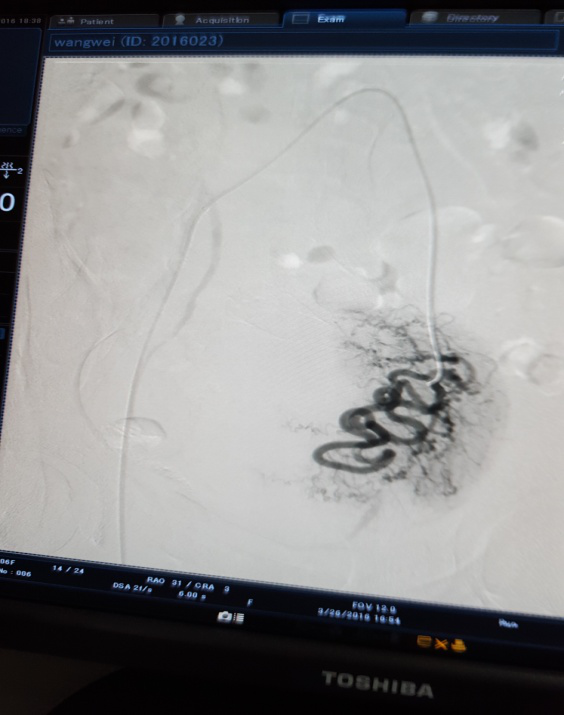

治疗前 右侧                            治疗后 右侧分支血管消失

3月28日下午3点,在医院新导管室内,放射介入科主任张敏荣与任长德、李可峰医师成功地完成了新导管室建成后首例子宫腺肌症介入手术。该患者女性、40岁,因患子宫腺肌症,造成腹痛难耐,C臂下造影见:左子宫动脉增粗,分支数量增多、迂曲,用PVA颗粒栓塞迂曲的分支动脉,在妇产科保驾下,手术操作顺利。经过几天的对症治疗,各项检查指标符合出院标准,现病人已出院家中休养。该项手术的成功开展,又一次填补了市中医院该项之空白。